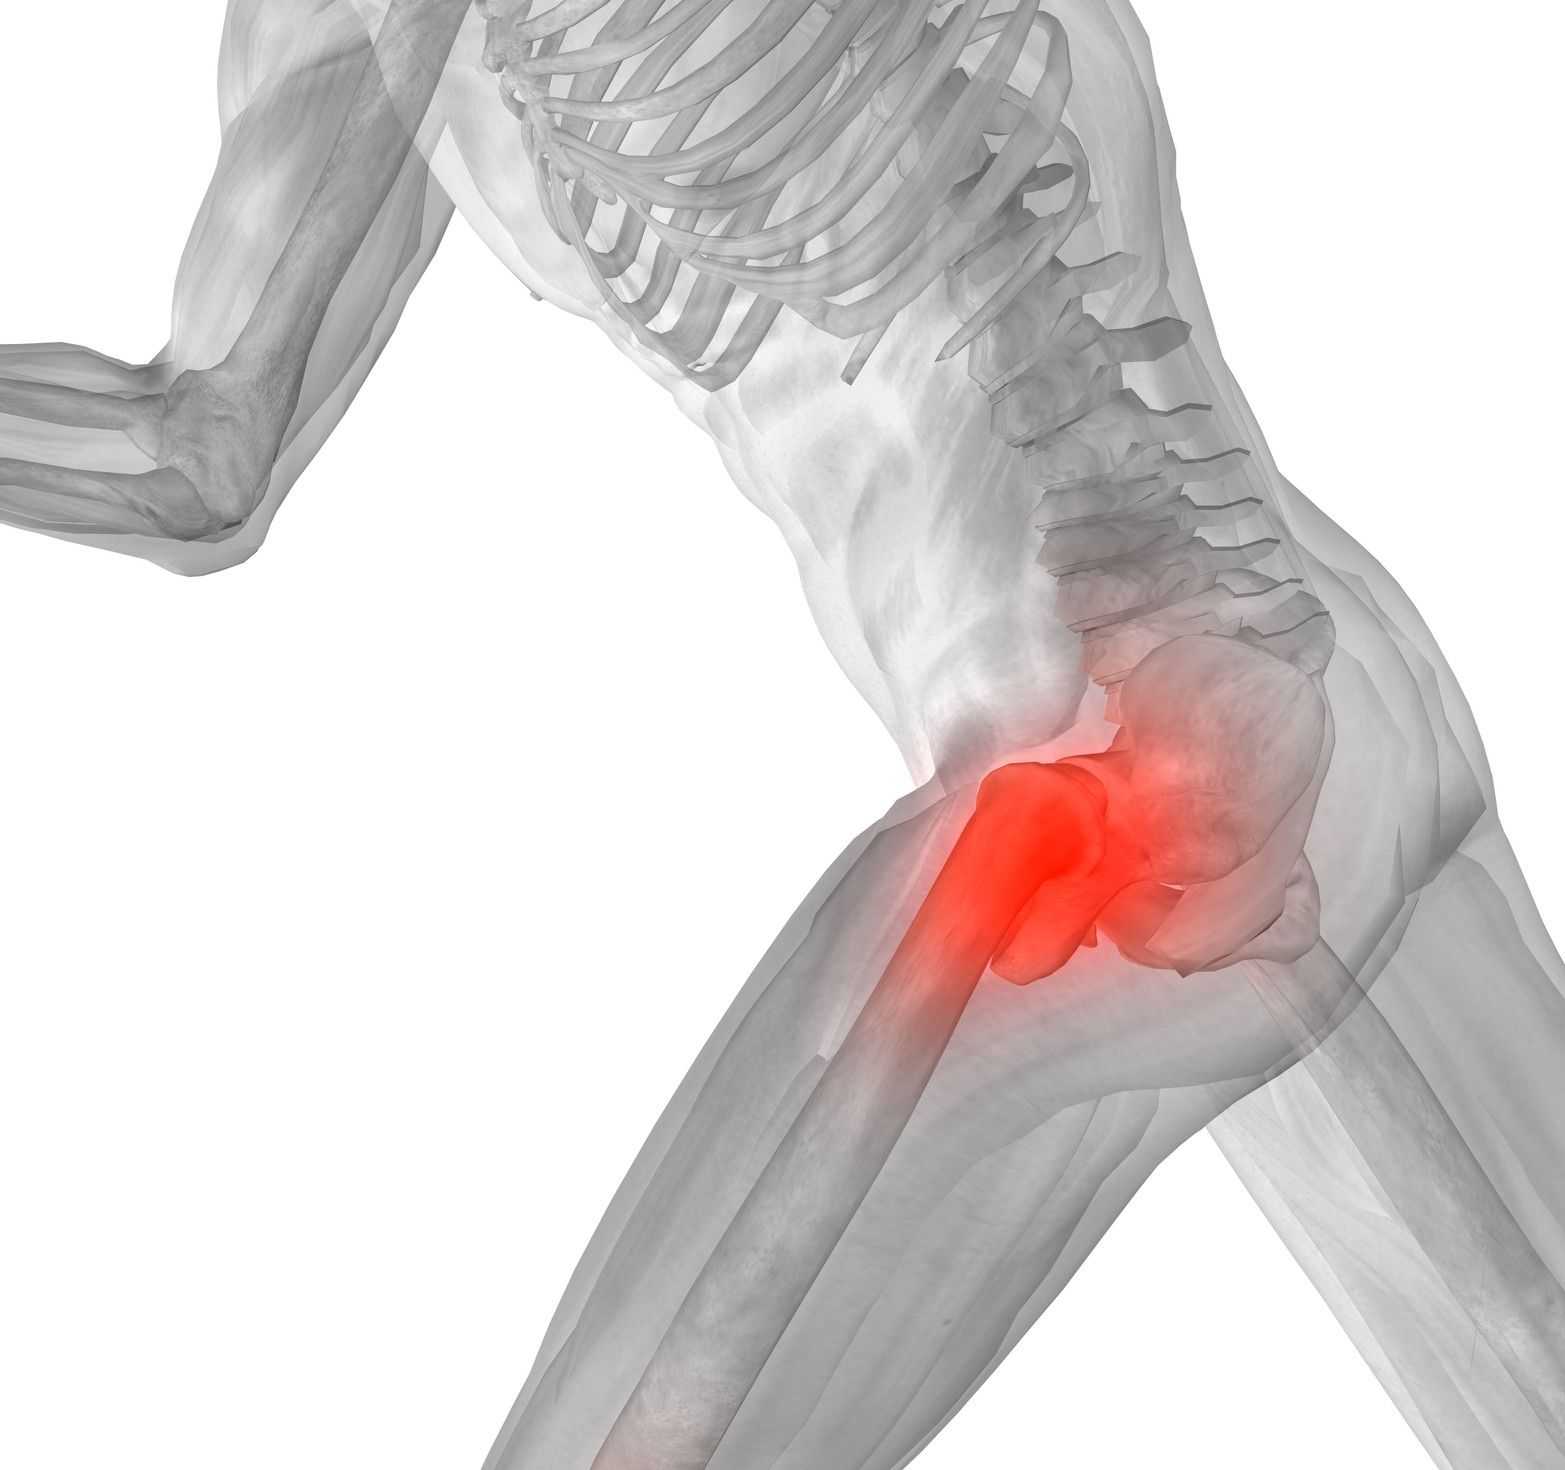

Здоровье суставов: Трохантерит и его влияние на мышцы